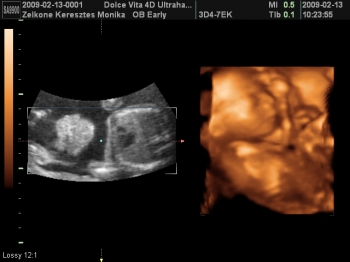

Az 1. Női Klinikán voltam szívuh-n.